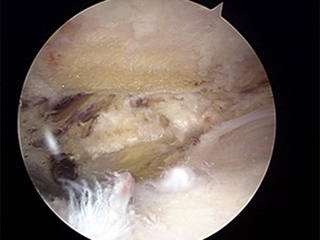

견봉성형술 전